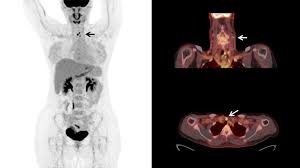

Pet/ct, which is a combination of positron emission tomography (pet) with computerized tomography (ct), is a powerful, essential tool for cancer detection and diagnosis.

The platform will enter a long tube where the pet scan is performed. Pet scans can show solid tumors in the brain, prostate, thyroid, lungs, and cervix. Pet scans can be used to: Positron emission tomography (pet) scans: Your healthcare provider may order a pet scan to check for signs of: The reality is that you cannot rely on a ct scan (or ultrasound, mri, or blood test) to tell you if you have cancer. Positron emission tomography (pet) scan. Doctors introduce a tracer into the system and areas with high chemical activity show up on the screen as bright spots. Pet/ct, which is a combination of positron emission tomography (pet) with computerized tomography (ct), is a powerful, essential tool for cancer detection and diagnosis. Before the scan, you receive an injection of a tracer called radioactive glucose. The scans can also evaluate the occurrence of colorectal, lymphoma, melanoma, and pancreatic tumors. However, as with most studies, there are a few exceptions. It is only with a pet/ct scan that you will know for sure.

Help diagnose and manage central nervous system disorders such as depression, epilepsy, alzheimer's and parkinson's disease. Because of this high level of chemical activity, cancer cells show up as bright spots on pet scans. Coronary artery disease, heart attack or other heart problems. With that being said, not all cancers can be detected by pet. A pet scan is similar to a ct scan; Pet is primarily used to diagnose cancer, cardiovascular disease, and neurologic disorders. Before the scan, you receive an injection of a tracer called radioactive glucose. Pet scans can help detect cancer and how far it has spread. The pet/ct scanner produces an image of the anatomy fused with the functional images of the use of sugar by cells. Doctors often order pet scans to stage a cancer or to assess whether treatment is working. Do all cancers show up on pet scan? The scans can also evaluate the occurrence of colorectal, lymphoma, melanoma, and pancreatic tumors. Brain disorders, such as brain tumors, epilepsy, dementia and alzheimer's disease.